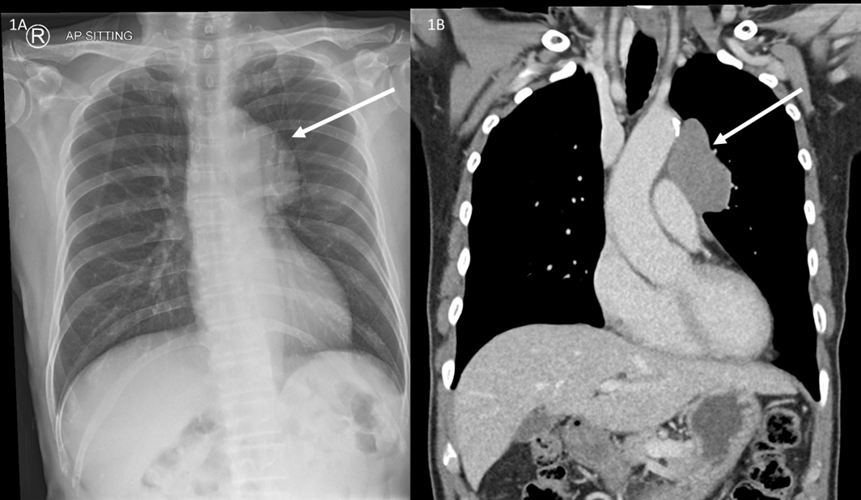

The Role of CT-Guided Optimal Fluoroscopic Projection Angle to Guide Stenting of Occluded Pulmonary Arteries

Yao Mi, MD, Mingwang Ding, MD, Yunshan Cao, MD, PhD

1-4